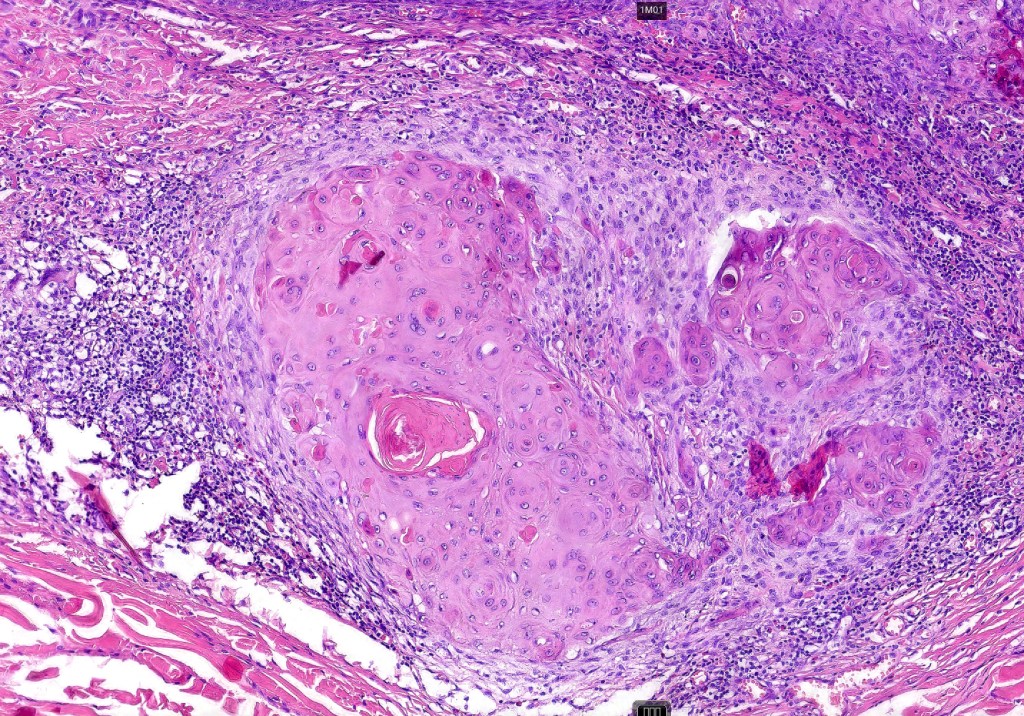

•Infundibular cyst lined by acanthotic squamous epithelium showing marked hypergranulosis, hyperkeratosis & parakeratosis

•Conspicuous, enlarged keratohyalin granules

•Koilocytosis

•Squamous eddies are often a prominent feature